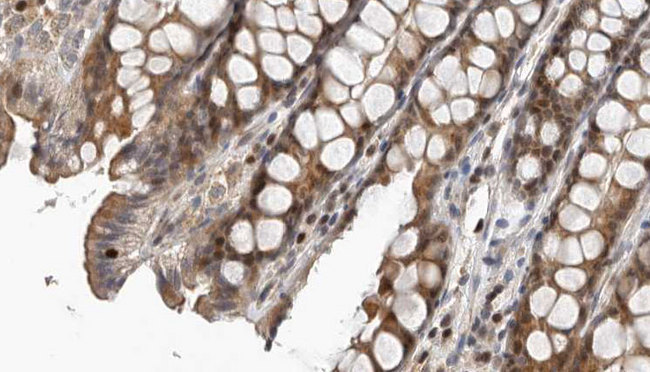

- Experimental details

- 1/100 staining human colon carcinoma tissue by IHC-P. The sample was formaldehyde fixed and a heat mediated antigen retrieval step in citrate buffer was performed. The sample was then blocked and incubated with the antibody for 1.5 hours at 22°C. An HRP conjugated goat anti-rabbit antibody was used as the secondary antibody.